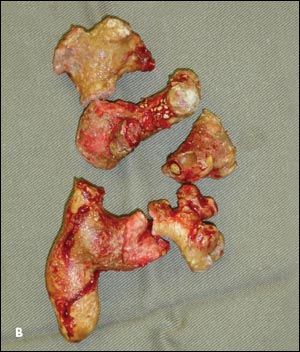

Figure 3 – A complicated staghorn stone is shown on a pretreatment radiograph (

) and after removal by open surgery (

B

).

Open surgery. Open surgery for renal calculi has now been supplanted by less invasive procedures.5 Studies have confirmed the advantages of endoscopic surgery (PCNL) over open surgery for staghorn stones.15,16 Open surgery is mainly reserved for patients with large, extensively branched, complex staghorn stones (Figure 3), those with altered renal anatomy, and those with coexisting renal abnormalities that require a simultaneous reconstructive open procedure. However, for a kidney with poor renal function (differential kidney function of less than 15%), simple nephrectomy might be more definitive and beneficial for the patient than multiple complicated endoscopic stone removal procedures.